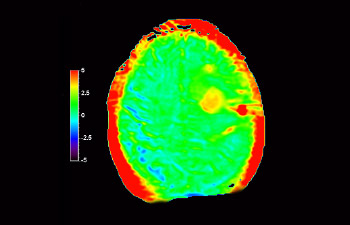

Brain image

Brain with glioblastoma

3D APT

Enhanced diagnostic confidence in neuro oncology